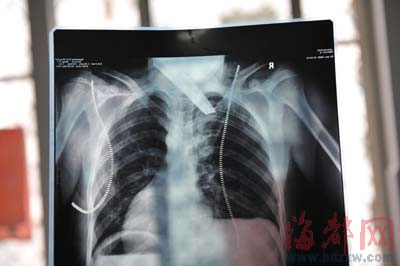

前晚,在第一醫(yī)院急救室,經(jīng)過4個多小時的搶救,醫(yī)生將匕首從小勇身上取出,發(fā)現(xiàn)這把匕首的刀尖扎斷了1厘米。由于小勇肺部被刺中,昨天上午,醫(yī)生再次進行了3個多小時的手術(shù),切除了受傷的部分肺,直到下午,小勇才挺過來!巴α艘灰,現(xiàn)在總算醒了過來。”楊女士一夜沒睡,守在手術(shù)室外7個多小時,生怕兒子再醒不過來。不過,由于傷勢嚴重,小勇目前戴著氧氣呼吸,仍未脫險。